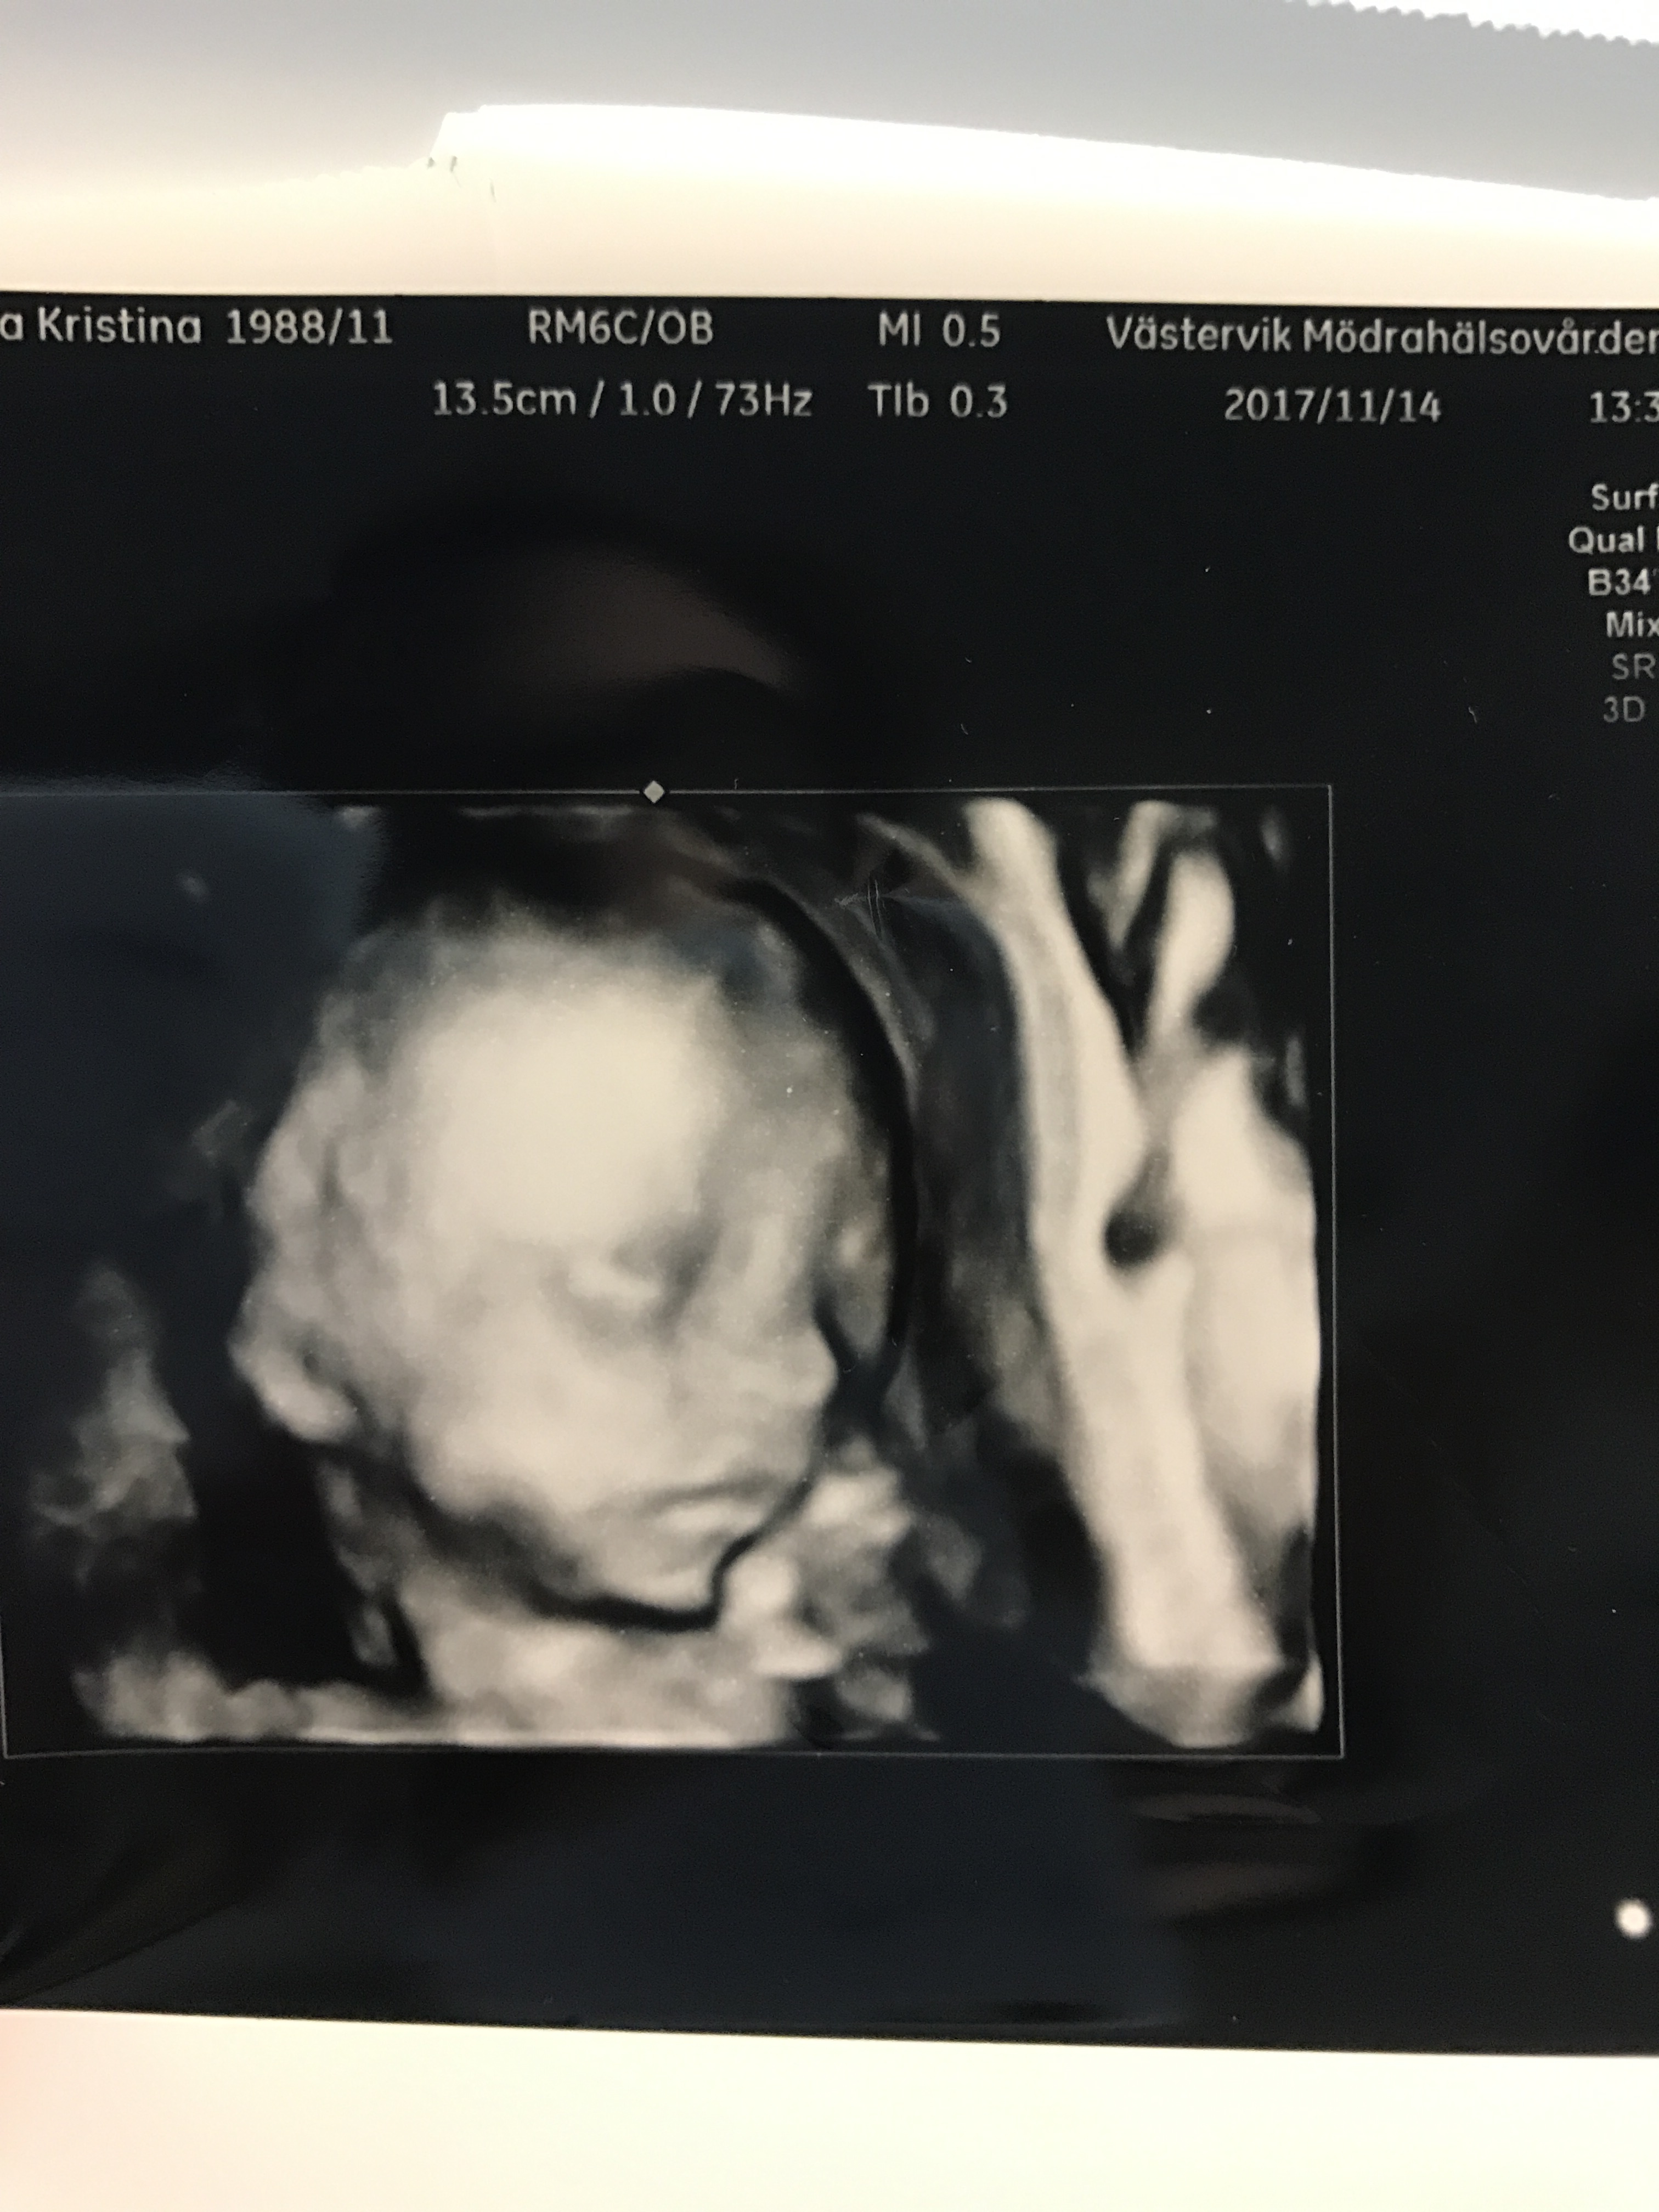

Idag var vi på ett extra ultraljud eftersom de hade utbildning på MVC och jag tydligen är lätt att göra ultraljud på. Så vi blev erbjudna att vara försöksobjekt.

Så mysigt att se vår lilla larv igen och idag visade han sig från sin bästa sida så de var väldigt nöjda. Så kul med 3D bilder också.